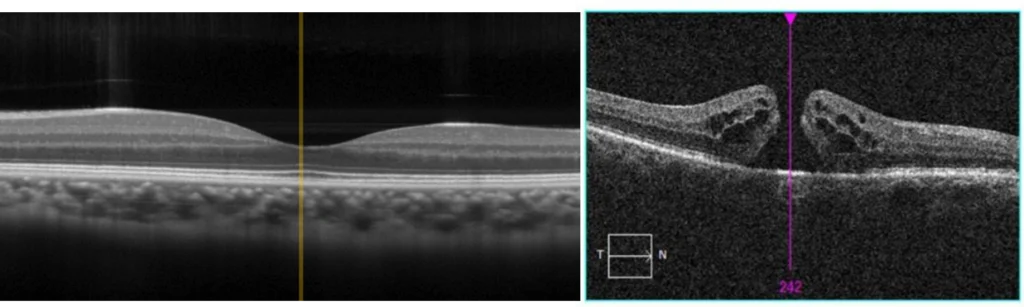

An ophthalmologist can examine your retina in order to diagnose an epiretinal membrane. Once the membrane is detected, there are two common photographic tests administered for assessing the extent of the damage to the underlying retina. These tests are fluorescein angiography (FA) and optical coherence tomography (OCT).

Optical coherence tomography is a newer epiretinal membrane assessment in which light waves are bounced off the retina to obtain a cross section image. No dye is used in this exam. Rather, the light waves map the retina, acting similarly to sonar waves mapping images of the ocean floor.